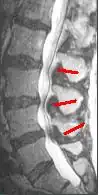

Helpful imaging may include x-rays, CT, CT myelogram, and magnetic resonance imaging (MRI), but MRI is preferred.[1] Abnormal MRI findings may be present in two-thirds of asymptomatic individuals, and imaging findings of spinal stenosis do not correlate well with symptom severity. Therefore, imaging findings must be considered in the context of a patient's history and physical exam when seeking a diagnosis.[2] The evidence for using objective imaging findings to define NC has been conflicting.[12]

Degenerative disc disease (DDD) may trigger the pathogenesis of neurogenic claudication.[17] When intervertebral discs degenerate and change shape in DDD, the normal movements of the spine are interrupted. This results in spinal instability and more degenerative changes in spinal structures including facet joints, ligamentum flavum, and intervertebral discs. These pathologic changes result in narrowing of the vertebral canal and neurovascular compression at the lumbosacral nerve roots.[1][18] The compression of these spinal nerve roots that control sensation and movement in the lower body results in the tingling, pain and weakness NC patients often experience. However, because the severity of symptoms does not correlate well with the degree of stenosis and nerve root compression, a clear understanding of the specific pathogenesis remains challenging.[7]

These changes in blood flow may occur during back extension when shifts in vertebral structures and ligaments narrow the spinal canal and compress the neurovasculature.[15] Compared to a neutral position, extended spines exhibit 15% less cross-sectional area of the intervertebral foramina, and nerve root compression is present one-third of the time.[10] These dynamic changes in the shape of the spinal canal are more pronounced in individuals with spinal stenosis. The amount of narrowing may be 67% in LSS compared to 9% in healthy spines.[1]